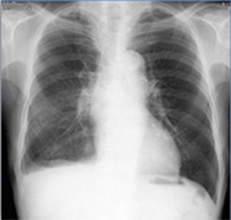

胸部経時差分処理

Temporal Subtraction処理

Temporal Subtraction処理は、独自のアルゴリズム補正をもとに、胸部画像の現在と過去の差分画像を生成する画像処理技術です。

がん予防重点健康教育及び、がん検診実施のための指針では、胸部エックス線写真の読影方法として二重読影の結果必要と判断される場合は、比較読影を行うことが示されています。*

しかし、画像を細かな部分まで見比べるには時間がかかり、また、小さな変化は見逃してしまう可能性があります。

そこで、現在と過去の差分画像を生成し「変化の有無」を可視化することで、診断精度の向上と時間短縮が期待でき、胸部読影を強力にサポートします。